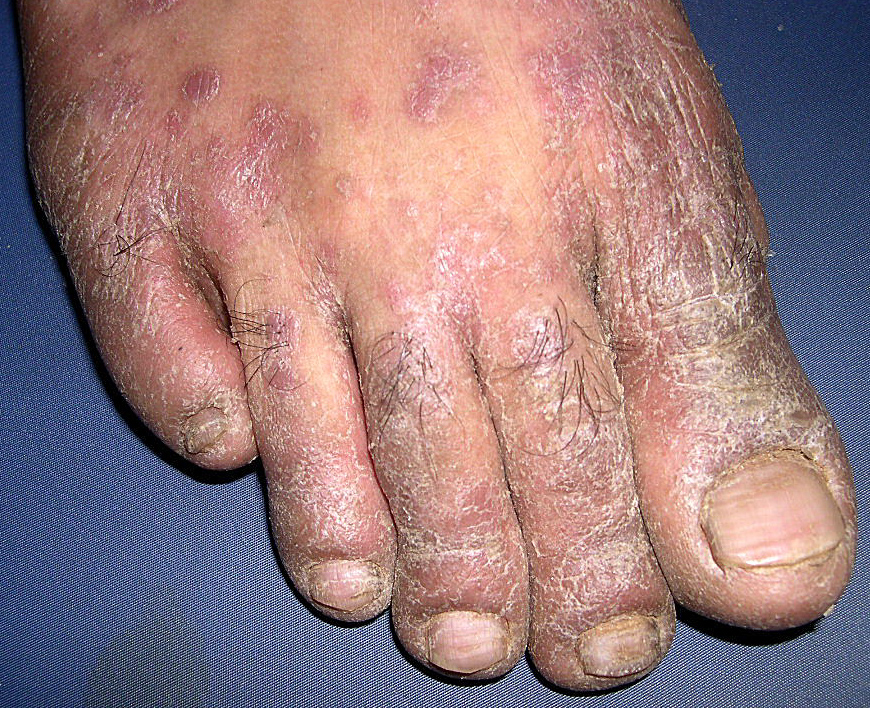

Psoriasis_erythrodermic = الأحمرية الصدفية